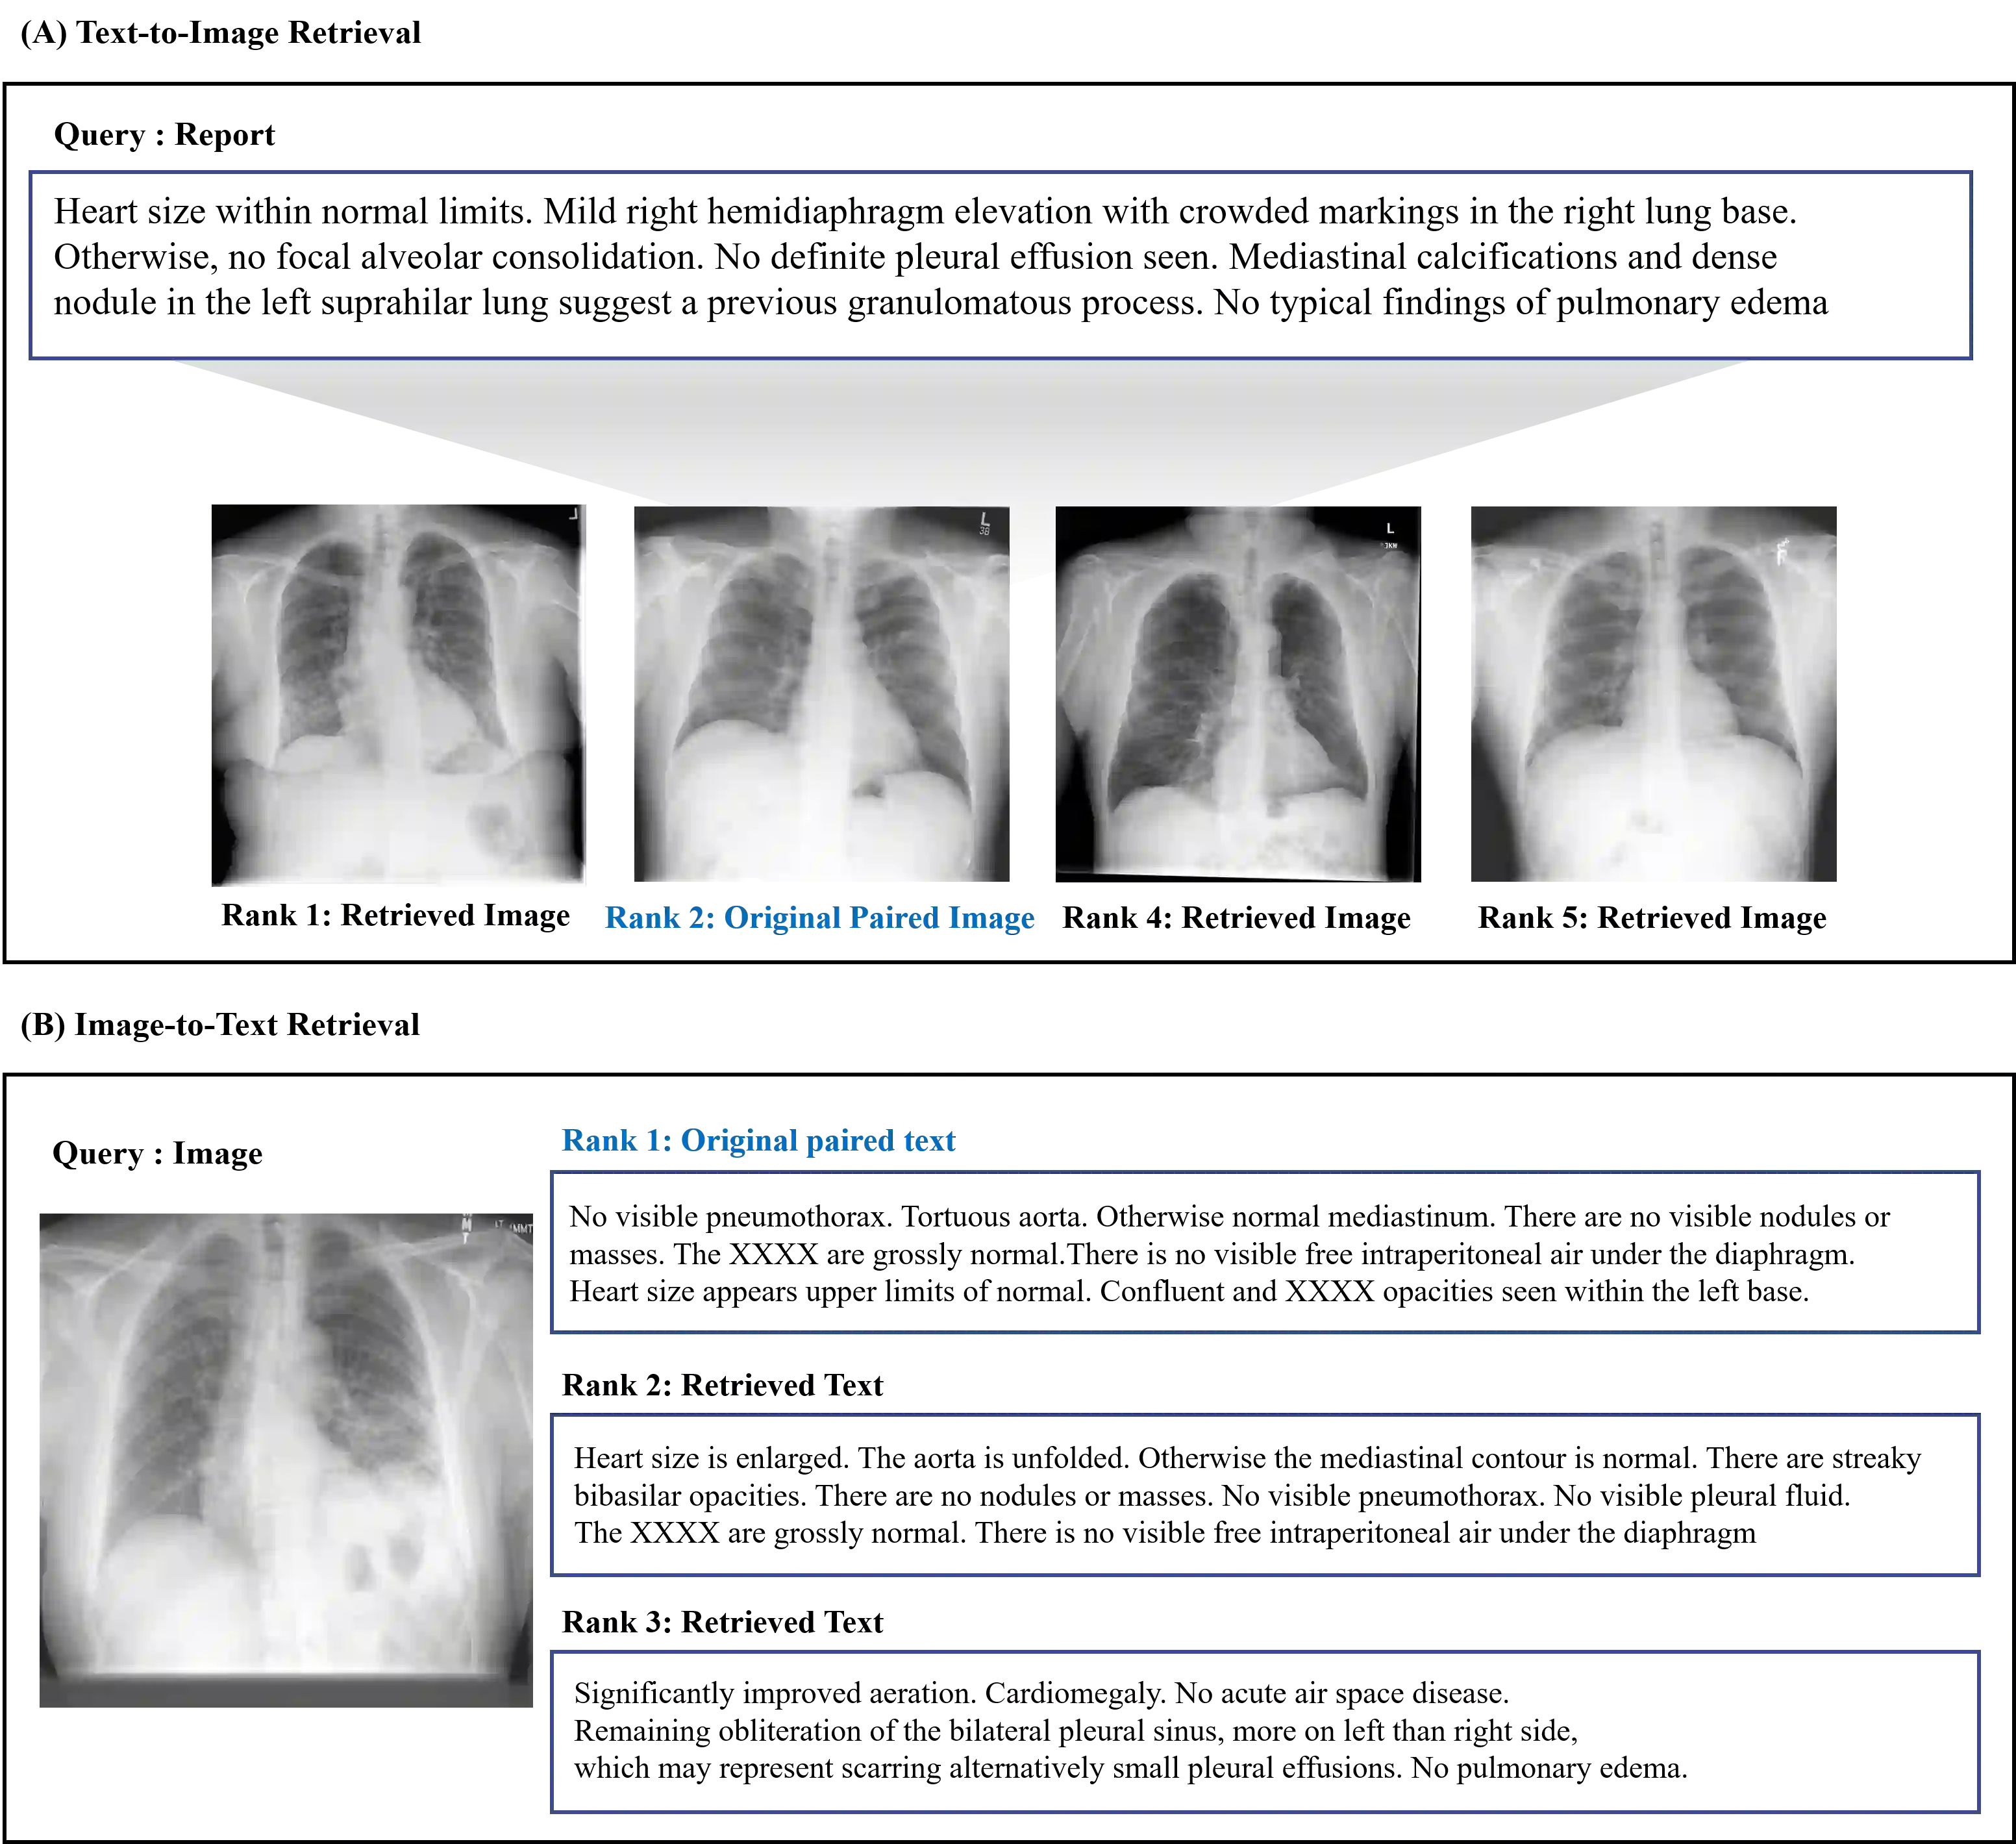

Recently a number of studies demonstrated impressive performance on diverse vision-language multi-modal tasks such as image captioning and visual question answering by extending the BERT architecture with multi-modal pre-training objectives. In this work we explore a broad set of multi-modal representation learning tasks in the medical domain, specifically using radiology images and the unstructured report. We propose Medical Vision Language Learner (MedViLL) which adopts a Transformer-based architecture combined with a novel multimodal attention masking scheme to maximize generalization performance for both vision-language understanding tasks (image-report retrieval, disease classification, medical visual question answering) and vision-language generation task (report generation). By rigorously evaluating the proposed model on four downstream tasks with two chest X-ray image datasets (MIMIC-CXR and Open-I), we empirically demonstrate the superior downstream task performance of MedViLL against various baselines including task-specific architectures.